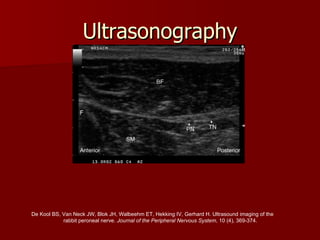

Ultrasonography De Kool BS, Van Neck JW, Blok JH, Walbeehm ET, Hekking IV, Gerhard H. Ultrasound imaging of the  rabbit peroneal nerve.  Journal of the Peripheral Nervous System , 10 (4), 369-374. PN, peroneal nerve; TN, tibial nerve; BF, biceps femoris muscle;  SM, semimembranosus muscle; F, femur

Ultrasonography De KoolBS, Van Neck JW, Blok JH, Walbeehm ET, Hekking IV, Gerhard H. Ultrasound imaging of the rabbit peroneal nerve. Journal of the Peripheral Nervous System , 10 (4), 369-374. PN, peroneal nerve; TN, tibial nerve; BF, biceps femoris muscle; SM, semimembranosus muscle; F, femur